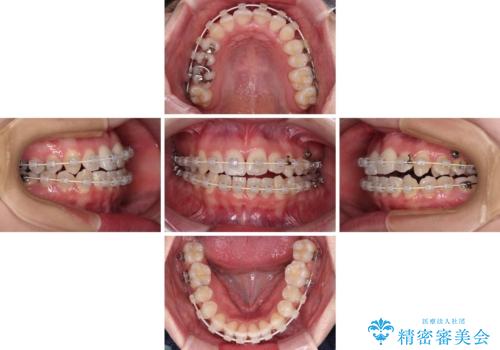

- 矯正装置

- 審美装置

- 治療計画

- 上下前歯のデコボコを気にして来院された患者様です。

上顎骨の横幅が狭く、奥歯は上顎よりも下顎が外側にある咬合状態でした。

歯列矯正では基本的に骨格を改善することはできませんが、急速拡大装置(MARPE)を使用することで上顎骨を側方に拡大させることができ、咬合状態を大きく改善することができます。

事前に急速拡大装置で側方拡大を行い、上下を目立たないワイヤー装置により歯列を整えていくこととしました。